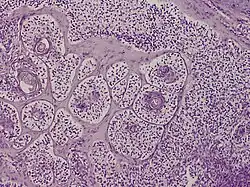

Trichilemmal carcinoma is a cutaneous condition reported to arise on sun-exposed areas, most commonly the face and ears.[1]: 674